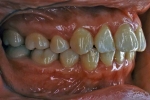

| 治療後2年経過時